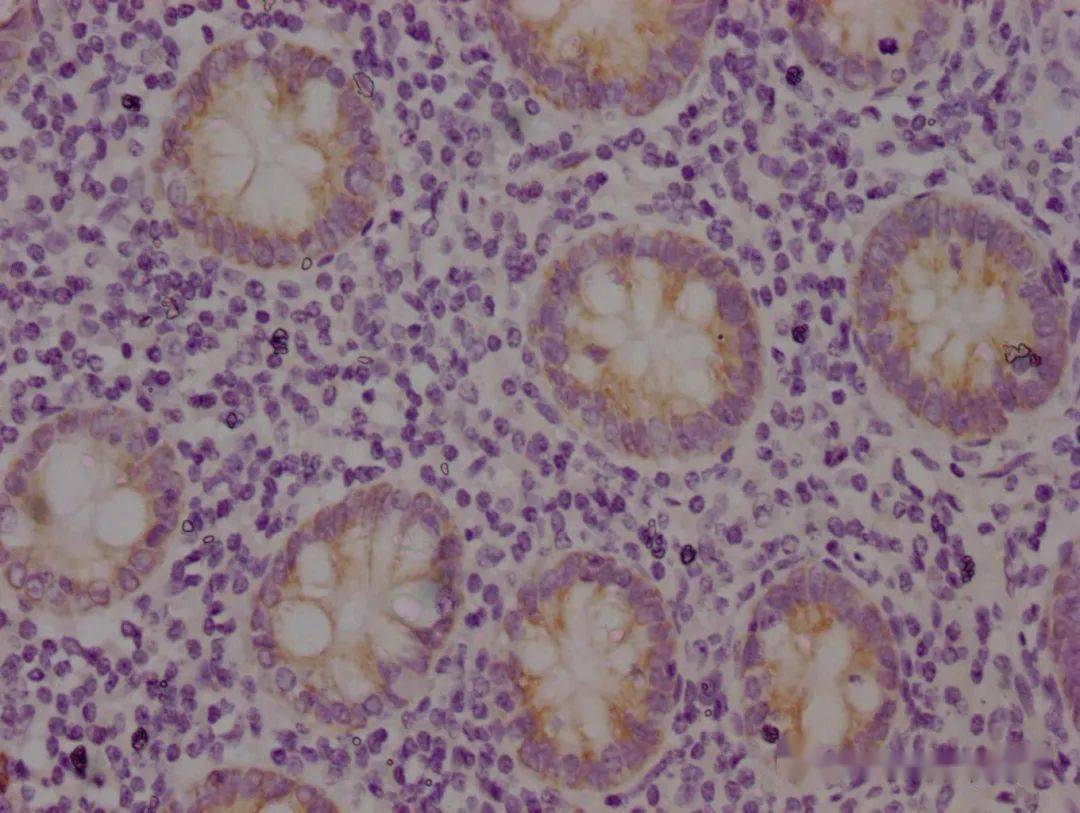

约20%瘤细胞cd45ro阳性(ihc染色×400)